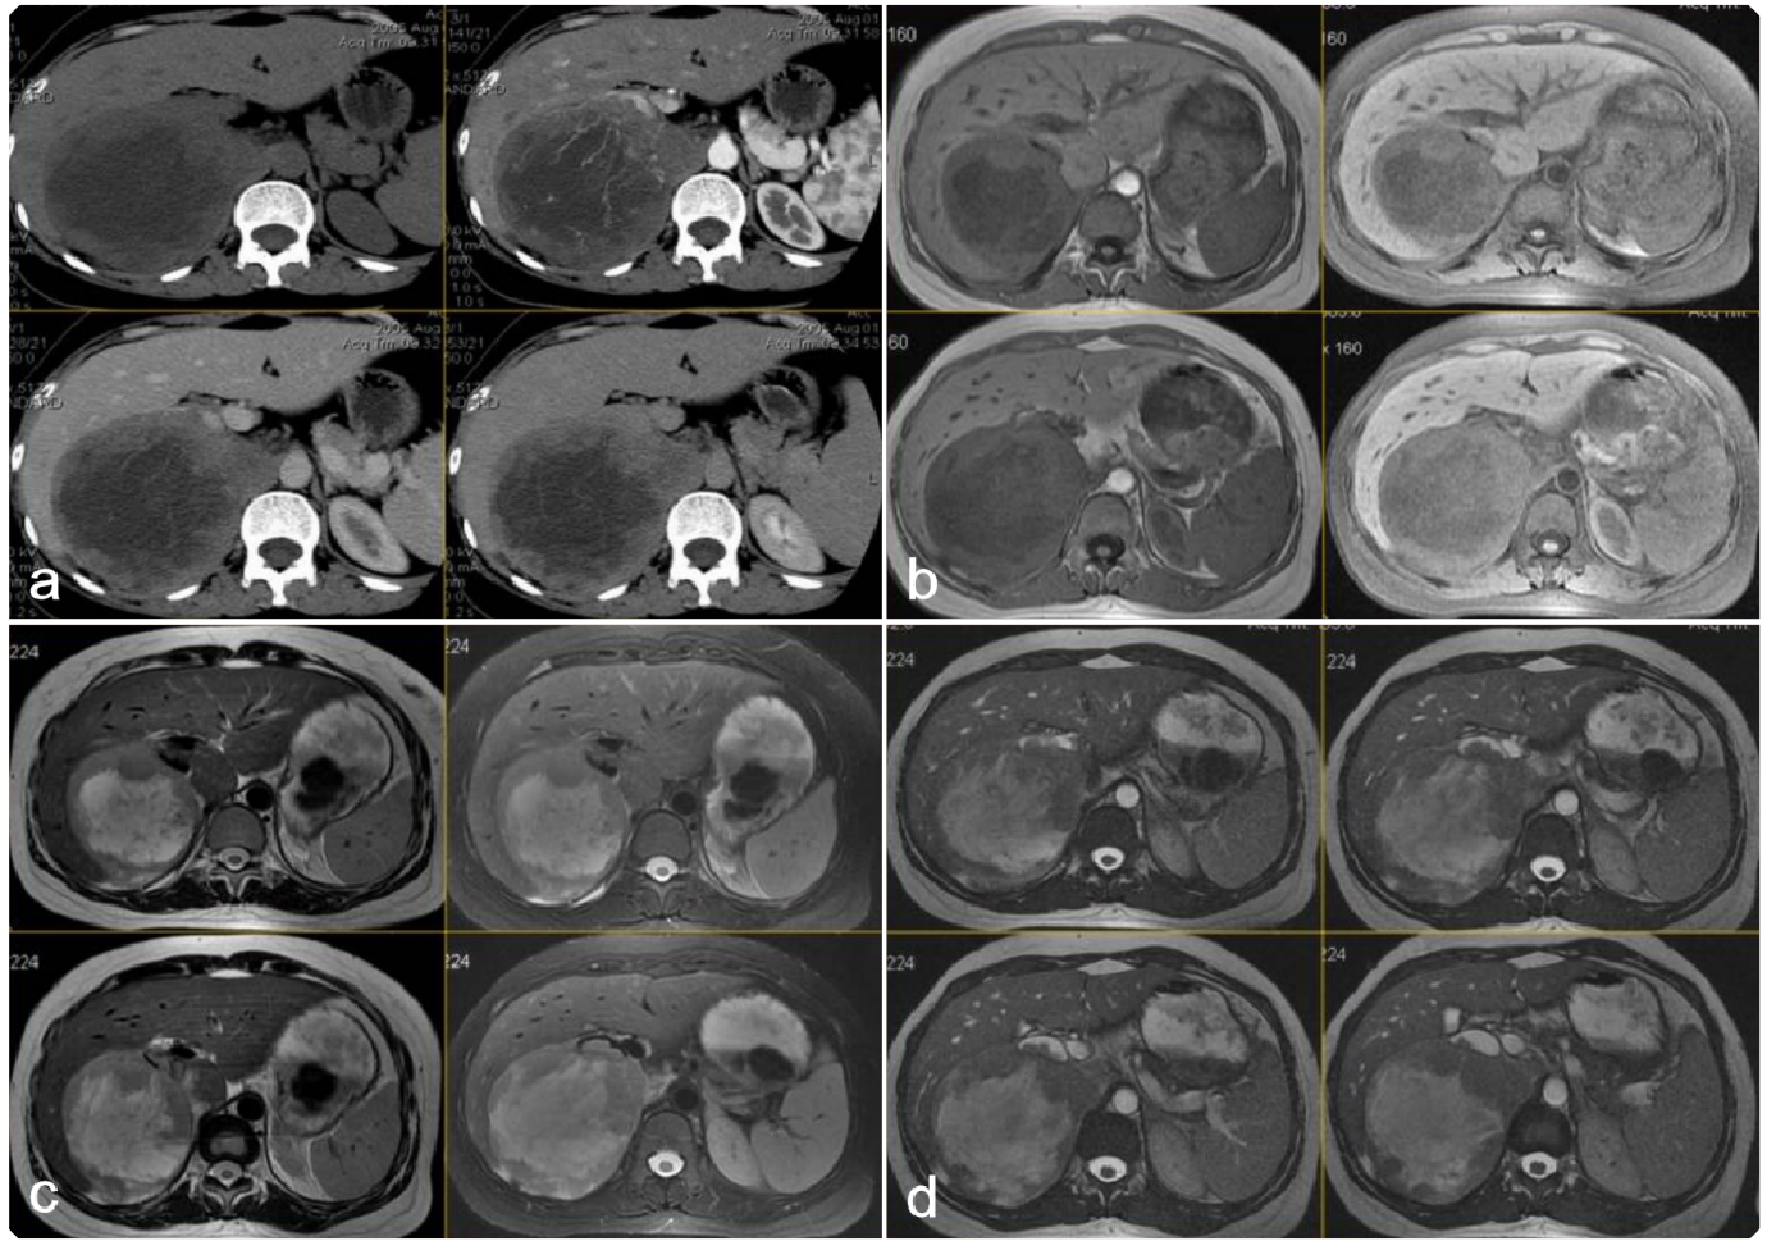

917bfe88330e9a51bacfc381b0a24818.png 病例 6:腹膜后平滑肌肉瘤2例

(① 血管内外;② 血管腔外)① 腹膜后肿块可见侵犯右肾血管、下腔静脉,密度不均匀,有囊变坏死,增强后边缘性延迟环状强化。② 腹膜后肿块与右肾血管,下腔静脉及腹主动脉分界不清,肿块密度不均匀,内可见囊变坏死区及高密度灶(平滑肌肉瘤瘤内如有出血,低密度区内可见高密度出血影,但通常不钙化),增强扫描呈明显不均匀强化,囊变区未见强化。